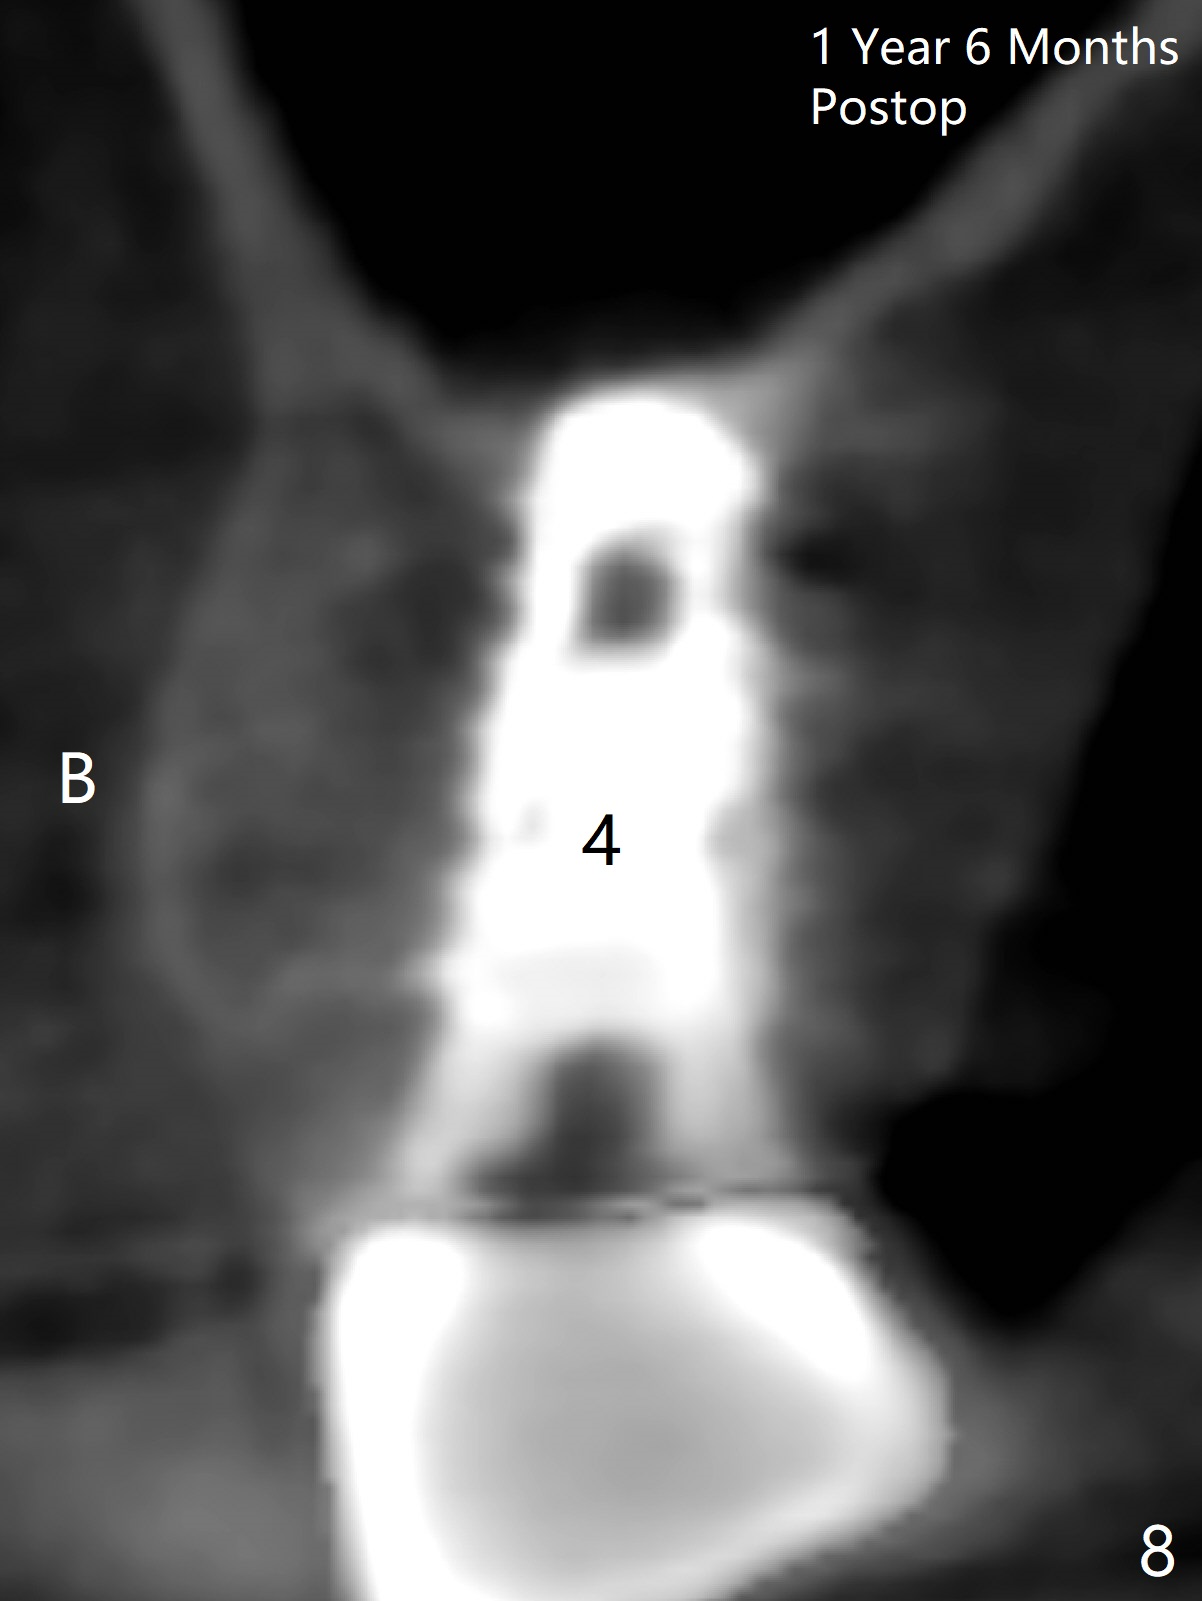

At the healed site (#5), insertion torque of a 4x11 mm implant is >50 Ncm (Fig.4). Because of supraeruption of the tooth #28 (Fig.6 arrow), a healing abutment (4x2 mm) is placed at #5 (data not shown), while a pair abutment (4.5x4(2) mm) is placed at #4 (Fig.4,6). In fact a splinted provisional is placed at #4 and 5 with a low occlusal table. There is no apparent bone loss 1 years 5 months postop (Fig.7). In fact the implants either perforate the palaatal or buccal (B) plate, as revealed by CBCT (1 year 6 months postop, immediately post cementation, Fig.8,9). It appears necessary to have guided surgery and smaller implant in the narrow ridge.